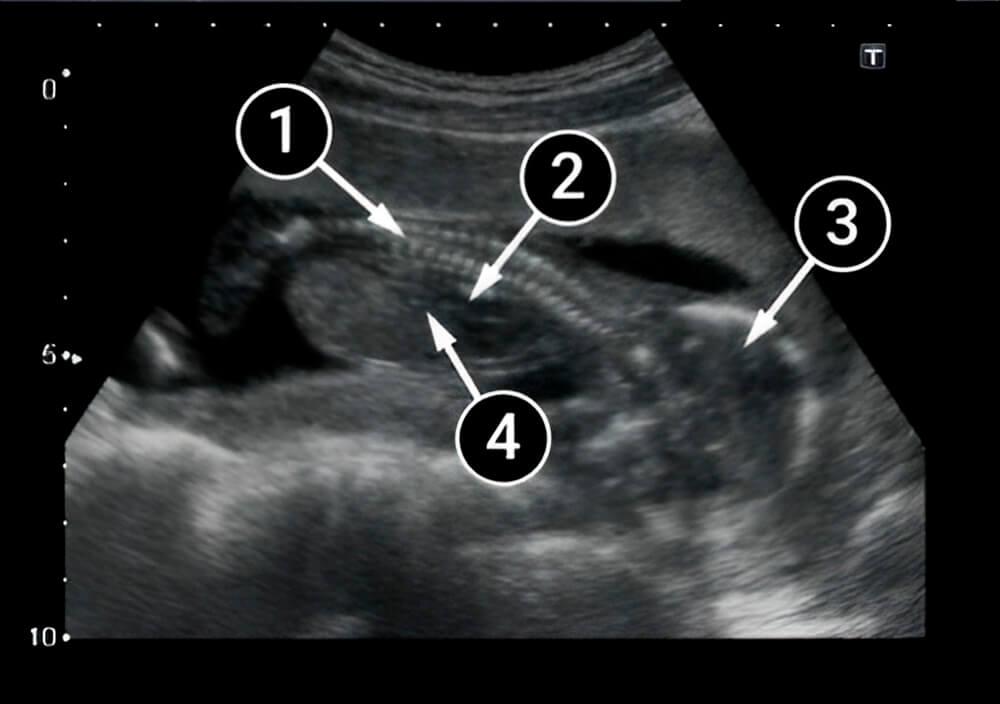

Lo que podemos ver en un ultrasonido

En esta imagen se puede ver al bebé acostado boca arriba. La posición permite ver la columna y las costillas (líneas claras, blancas y paralelas).

Los brazos y piernas del bebé no son visibles aquí, pero podemos ver el pecho, distinguible de la cavidad abdominal, y los intestinos dentro del abdomen. El contorno delgado y oscuro es el diafragma y se pueden ver los espacios intercostales.